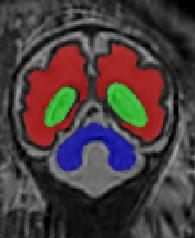

Limiting failures of machine learning systems is of paramount importance for safety-critical applications. In order to improve the robustness of machine learning systems, Distributionally Robust Optimization (DRO) has been proposed as a generalization of Empirical Risk Minimization (ERM). However, its use in deep learning has been severely restricted due to the relative inefficiency of the optimizers available for DRO in comparison to the wide-spread variants of Stochastic Gradient Descent (SGD) optimizers for ERM. We propose SGD with hardness weighted sampling, a principled and efficient optimization method for DRO in machine learning that is particularly suited in the context of deep learning. Similar to a hard example mining strategy in practice, the proposed algorithm is straightforward to implement and computationally as efficient as SGD-based optimizers used for deep learning, requiring minimal overhead computation. In contrast to typical ad hoc hard mining approaches, we prove the convergence of our DRO algorithm for over-parameterized deep learning networks with ReLU activation and a finite number of layers and parameters. Our experiments on fetal brain 3D MRI segmentation and brain tumor segmentation in MRI demonstrate the feasibility and the usefulness of our approach. Using our hardness weighted sampling for training a state-of-the-art deep learning pipeline leads to improved robustness to anatomical variabilities in automatic fetal brain 3D MRI segmentation using deep learning and to improved robustness to the image protocol variations in brain tumor segmentation. Our code is available at https://github.com/LucasFidon/HardnessWeightedSampler.